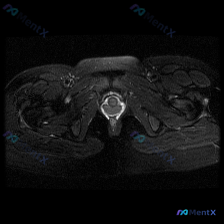

看到这张踝关节MRI,问题问有什么异常,很多人第一反应就是看到软组织积液,但其实背后藏着更关键的问题,我整理一下完整的分析思路给大家。 病例影像基础信息 这是一张踝关节MRI T2序列轴位影像,我们先把所有能看到的征象理清楚: 1. 骨骼结构:影像中心是距骨横截面,皮质骨低信号、骨髓中等信号,骨质轮...

看到这个踝关节MRI的病例,整理了完整的影像资料和分析思路,和大家分享讨论。 病例影像基础信息 这是踝关节MRI T2加权轴位图像,扫描层面为踝关节远端,可见距骨体及周围软组织结构,图像对比度满足观察要求,T2加权像液体呈高信号。 核心影像发现 1. 骨结构:距骨及周围骨性结构骨髓无异常高信号,骨皮...

刚看到这份踝关节MRI读片需求,整理了完整的观察和分析思路分享给大家。 病例基本影像信息 本次读片基于踝关节MRI-T2序列轴位图像,扫描层面为踝关节远端轴位,可清晰辨认胫骨、腓骨、距骨以及后方跟腱等正常解剖结构。T2序列对液体和水肿敏感,正常肌腱韧带应为低信号(黑色),液体/水肿为高信号(白色)。...

刚整理完一份踝关节MRI的读片分析,关于软组织积液的鉴别思路挺典型,分享给大家一起讨论。 病例影像基本信息 这是一份踝关节MRI T2序列轴位影像,扫描层面为距骨体水平,显示踝关节及周围软组织结构: 1. 骨骼表现:距骨及周围骨性结构骨皮质完整,骨髓信号无局灶异常高信号,排除明显骨挫伤、骨折或骨髓水...

刚看到这张踝关节T2轴位MRI,我整理一下影像表现和分析思路,跟大家讨论一下。 病例影像基本信息 这是踝关节轴位T2加权MRI,液体呈高信号(亮白色),骨皮质、肌腱韧带呈低信号(黑色)。 先看基础结构: - 骨性结构:胫骨、腓骨、距骨截面可见,骨髓信号均匀,没有明显骨质破坏或异常骨髓水肿 - 肌腱结...

最近看到一份踝关节MRI的影像分析,整理了整个诊断思路分享给大家,一起讨论下。 病例影像基本信息 这是踝关节轴位T2加权MRI扫描,核心发现整理如下: 1. 骨骼结构:胫骨、腓骨、距骨骨皮质完整,没有骨折线,骨髓信号均匀,无明显弥漫性骨髓水肿 2. 肌腱韧带:内外侧肌腱、跟腱走行正常,信号均匀,无腱...

今天整理了一份踝关节MRI的读片分析,核心问题是影像发现「软组织积液」该怎么判断,分享出来大家一起讨论。 病例影像基础信息 这是一份踝关节轴位T2加权MRI(T2WI)的读片报告,核心信息整理如下: 1. 骨骼结构:胫骨远端、距骨骨髓信号正常,无骨髓水肿、骨质破坏,皮质完整,未见骨折线 2. 关节结...